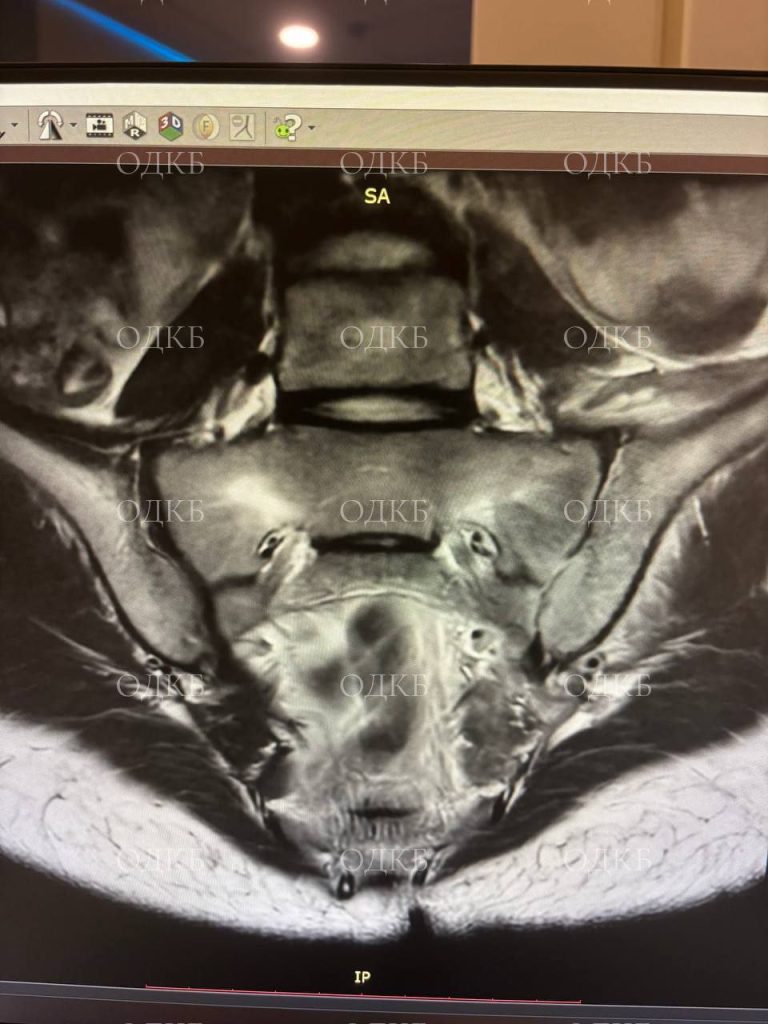

Специалисты провели полное обследование ребёнка: сделали КТ, МРТ, УЗИ, забрали анализы. Симптомы долго не позволяли чётко определить, какой орган тела девочки поражён. Симптомы очень схожи с клиникой «острого живота», артритом, радикулитом и почечной коликой. Ребёнок находился в вынужденном положении, активные движения в ногах были ограничены из-за сильных болей.

Необходимо было быстро принять верные решения, чтобы помочь девочке. Рентгенологи и врачи УЗИ увидели признаки сакроилеита, очаг поражения и деструктивные изменения в крестцово-подвздошном суставе. Определить, был ли это гнойный процесс или клиника артрита, врачи смогли только во время операции.

Очаг поражения был расположен глубоко внутри таза. Специалисты выявили абсцесс в проекции КПС. Если бы врачи вовремя не установили правильный диагноз и не устранили гной, он мог распространиться в брюшной полости, спинно-мозговом канале, и тазобедренном суставе. Это привело бы к более тяжёлым заболеваниям, и девочка была бы прикована к инвалидному креслу.